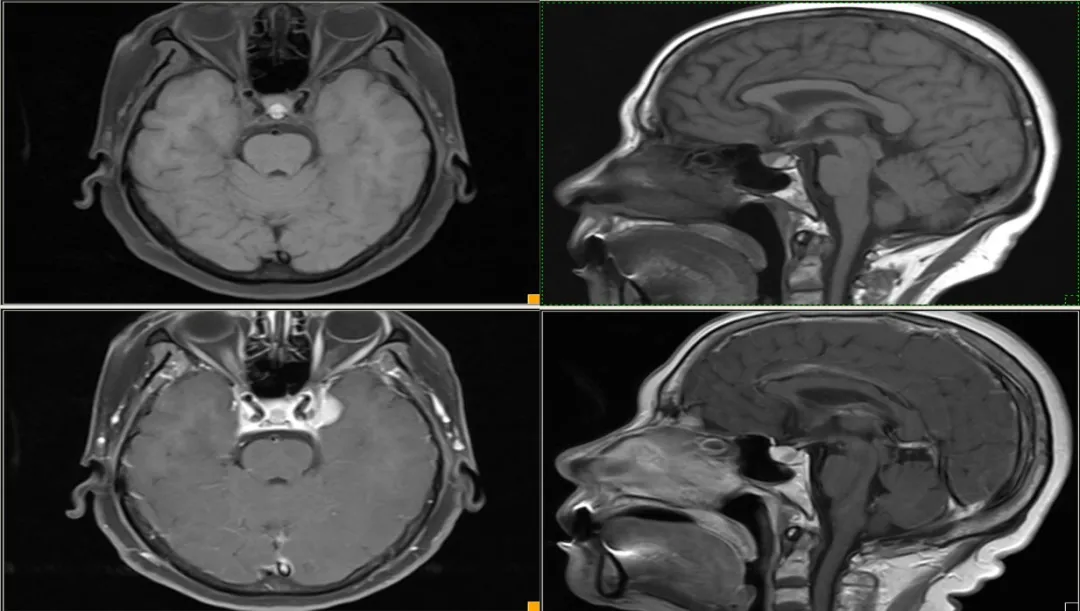

case 15:一年半前偶然发现,无明显症状,怀疑垂体瘤卒中,服用过一段时间溴隐亭,后经北京天坛医院诊断 Rathke 囊肿后后停药,现复查较前片无变化。

看完 14 个病例,一起来认识这个表现多样的 Rathke’s囊肿

形态信号异常,与垂体瘤卒中难以鉴别,但与患者既往检查片比较无异常改变,遂考虑囊肿可能

T1WI 高信号症状性 RCC 与出血性垂体瘤卒中鉴别:

• 冠状面对称、体积较小、信号均匀、增强边界光滑清晰、囊内结节提示→RCC。

• 体积大,冠状面不对称、信号不均匀、增强边界毛糙、鞍旁结构受侵、分隔征、液液平面征则提示→垂体瘤卒中。